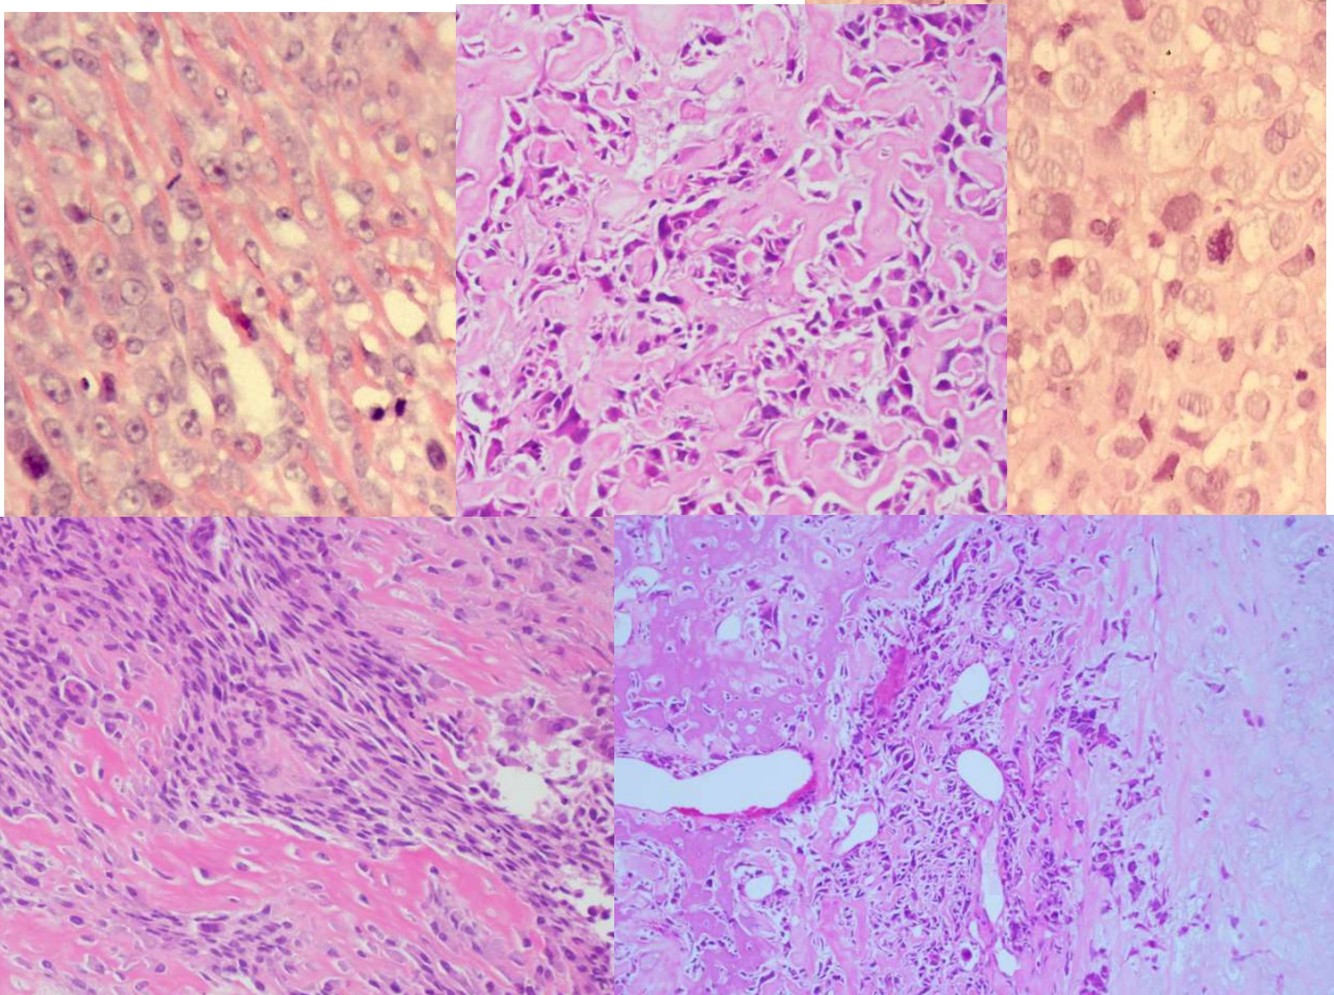

Chondrosarcoma Subtypes (5)

Chondrosarcoma Subtypes

CONVENTIONAL CHONDROSARCOMA

SECONDARY CHONDROSARCOMA

DEDIFFERENTIATED CHONDROSARCOMA

CLEAR CELL CHONDROSARCOMA

MESENCHYMAL CHONDROSARCOMA